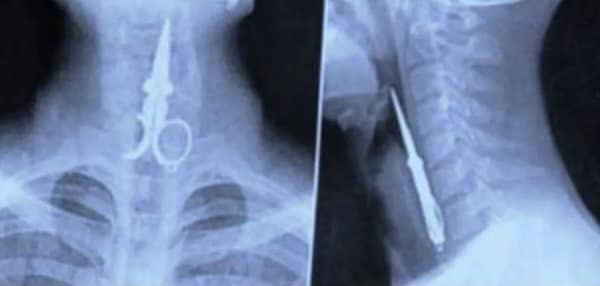

Weird xray photos

I used to think that nothing could surprise me anymore—until I stumbled upon some weird x-ray photos that made me reconsider my stance on human ingenuity (or lack thereof). Apparently, some people have a knack for getting objects lodged where they absolutely shouldn’t be. If you’ve ever wondered how not to use everyday items, these images might provide some unintended guidance.

This collection showcases 31 bizarre x-ray images that defy logic and anatomy textbooks alike. Each photo reveals unexpected objects making cameo appearances inside the human body, turning medical imaging into a gallery of the absurd. From common household items inexplicably found in unusual places to anomalies that would leave even seasoned doctors scratching their heads, these images offer a perplexing glimpse into the more “creative” side of medical emergencies. They highlight the intersection of curiosity, misadventure, and perhaps a dash of poor decision-making, all captured through the lens of radiology.